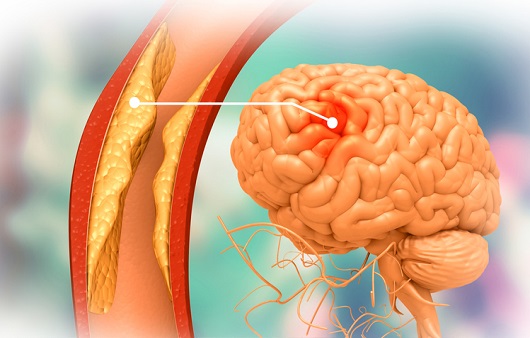

뇌혈관이 막히거나 터지는 질환을 부르는게 뇌졸중이고 그 중 뇌혈관이 막히는게 뇌경색 그리고 뇌혈관이 터지는 것을 뇌출혈이라고 합니다. 뇌졸중은 영구적인 손상이 많다고 하며 증상에 따라 전신이나 육체 일부 기능이 마비되는 등의 극심한 후유증이 남는 무서운 질병입니다 오늘은 뇌경색 초기증상에 대하여 알려드리도록 하겠습니다.

허혈성 뇌졸중은 발생 기전에 따라 대혈관 질환에 의한 뇌경색, 심인성 뇌경색 또는 심인성 뇌경색, 소혈관 질환 또는 틈새 뇌경색, 기타 드문 이유가 되는 것에 의한 뇌경색으로 나누어져요. 에피소드는 일정 기간 동안 증상이 완전히 가라앉는 경우입니다.

허혈성 뇌졸중의 대표적인 이유가 되는 것은 고혈압, 당뇨병, 고지혈증 등으로 인해서 뇌에 혈액을 전달하는 혈관에 동맥경화(동맥경화)가 발생하여 뇌로 가는 혈류를 차단하는 것입니다.